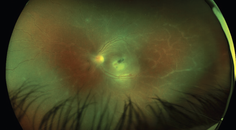

OCT provides high-resolution imaging of the vitreous and retina. This imaging modality can be used to quantify retinal thickness, to diagnose and monitor macular edema, and to monitor response to treatment (Figure 2). Large clinical studies, such as the RISE and RIDE studies, have used OCT rather than stereoscopic photographic images or clinical examination to evaluate and follow macular edema, as OCT facilitates a more accurate and objective assessment of the edema.14 In clinical practice, decisions regarding whether to refer and whether to treat or not to treat are often based solely on OCT findings.